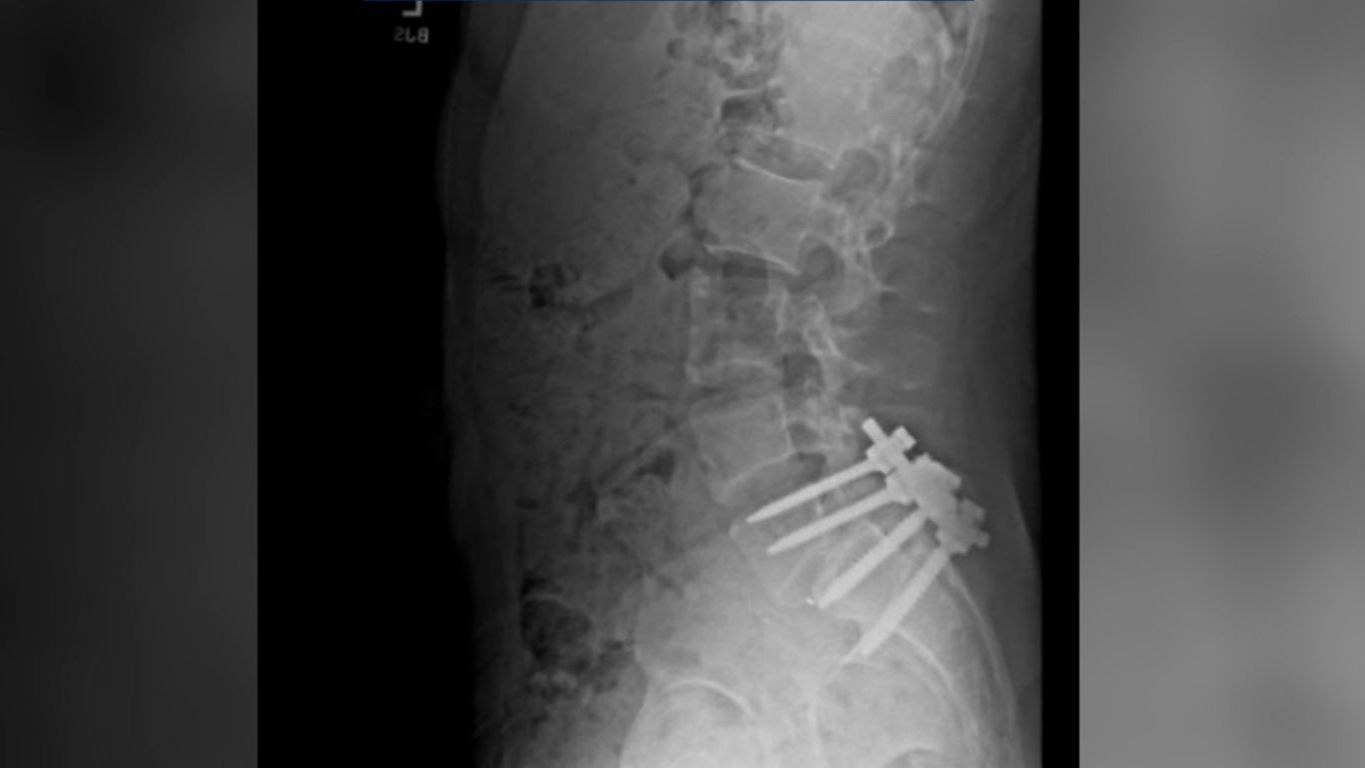

La radiografía que Luigi Mangione publicó en sus redes sociales, objeto de investigación

Cabe destacar que el joven publicó una radiografía en redes sociales, supuestamente suya, que muestra una columna vertebral tras ser operada (aparece en la cabecera de su perfil de X @pepmangione). Él entró en quirófano hace seis meses. Y nadie volvió a saber de él desde entonces, hasta que el pasado miércoles, presuntamente, reapareció para convertirse en el asesino de Brian Thompson.